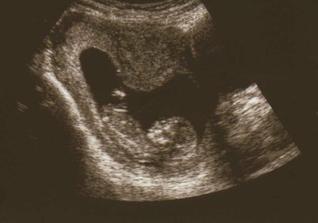

PM- 3.4., 2.5. jsem objevila dve carky. První potvrzení těhu 9.5.- na ultrazvuku jen bod, doktor mě pozval na kontrolu až 17., ale ja zmenila doktora, takže dalsi kontrola až 21.5...mimi už bylo vidět - 2 mm, tlouklo mu už "primitivní" srdíčko. Další kontrola 2.6. v 8 tt a 4 dnech - miminko bylo hezky vidět, je už 2,2 cm velké a dostala jsem krásnou fotku z UZV- je tam z profilu videt hlavicka. Další kontrola 26.6. - screening, odbery a downuv syndrom... Kontrola dopadla dobre, mimi ma ruce a nohy a vse je v normalu, uz ma 5, 3 cm! Je to maly akrobat.

21. 7., 15+4 - mereni nozky, obvodu hrudniku a hlavicky - vse v normalu. Tripple testy, cekame na vysledek...na UTZ byl i tatínek a nejvíce se mu líbilo, jak mimi bije srdíčko. A bude to ... holkaaa🙂